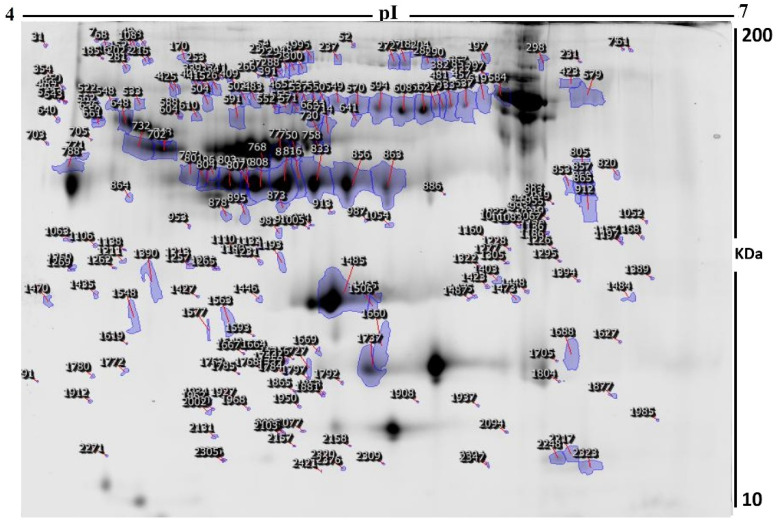

The current study assessed the difference in protein expression among 10 cannabis-exposed individuals and 10 controls (20 samples from 10 gels) using 2D-DIGE analysis technique before statistical analysis is performed with Progenesis software. Fluorescent protein profiles of a 2D-DIGE of control samples labelled with Cy3 are presented in Figure 1A. The CUD samples were labeled with Cy5 (Figure 1B), pooled internal control labeled with Cy2 (Figure 1C), and overlap of 2D-DIGE gels of samples labeled with Cy3/Cy5 (Figure 1D). A total of 1700 spots were identified on the gels, 156 were significantly different (ANOVA, p ≤ 0.05; fold-change ≥ 1.5) between the CUD and control groups (Figure 2). For alignment and further analysis, the spot patterns were reproducible across all 10 gels. The internal standard Cy2-labeled was included to perform normalization among the whole gels set in addition to the quantitative of the protein levels differential analysis. A total of 156 spots displayed a statistical significance among the two groups. These spots were manually excised from the preparative gel and underwent protein identification using MS.

Peptide mass fingerprints (PMFs) identified 121 out of 156 protein spots that were excised from preparative gel, MALDI-TOF. MS found 85 spots to be unique protein sequences. These sequences were matched to the SWISS-PROT database by Mascot search engine with high confidence scores (Table 2, Supplementary Table S2). The sequence coverage ranged from 4% to 85%. In few cases, the same protein variants were found at several locations on the gel (Table 2, Figure 2). Among the 121 proteins identified, 55 were upregulated and 66 were downregulated in the samples of CUD patients compared with that in the control subjects (Table 2, Figure 3). The significantly upregulated proteins included Apolipoprotein A-I (up 3.8-fold, p = 0.01), Alpha-1-antichymotrypsin (up 2.7-fold, p = 0.02), U3 small nucleolar RNA-associated protein 15 homolog (up 2.6-fold, p = 0.03), Zinc finger protein 550 (up 2.4-fold, p = 0.04), Haptoglobin-related protein (up 2.4-fold, p = 0.01), Spectrin beta chain, non-erythrocytic 4 (up 2.3-fold, p = 0.01), Keratin, type I cytoskeletal 10 (up 2.2-fold, p = 0.007), Dedicator of cytokinesis protein 9 (up 2.1-fold, p = 0.02), Haptoglobin (up 2.4-fold, p = 0.01), and Serine/threonine-protein phosphatase 2A regulatory subunit B’’ subunit gamma (up 2.0 fold, p = 0.05); a complete list is provided in Table 2. By contrast, the significantly downregulated proteins in CUD subjects included Hemoglobin subunit beta (down 5.0-fold, p = 0.05), Alpha-1-acid glycoprotein 2 (down 3.7-fold, p = 0.04), Rab GTPase-activating protein 1-like (down 2.9-fold, p = 0.02), and Ubiquitin domain-containing protein 1 (down 2.6-fold, p = 0.04) (Table 2, Supplementary Table S2). Among identified proteins: Inactive tyrosine protein kinase PEAK1, Transthyretin; Serotransferrin; Keratin, type I cytoskeletal 10; Apolipoprotein A-I; Ficolin-3; Vitamin D-binding protein; Haptoglobin; Keratin, type II cytoskeletal 1; Albumin; Alpha-1-antitrypsin; Retinol-binding protein 4, Outer dense fiber protein 2; Dynein heavy chain 3, axonemal; Parvalbumin alpha; Rab GTPase-activating protein 1-like; Structural maintenance of chromosomes protein 1A and Zinc finger protein 175 were found in ≥1 spot on the gels, which could be explained by post-translational modifications, cleavage by enzymes, or different protein species presence.